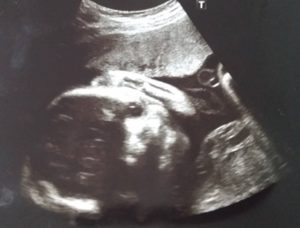

まずは妊娠後期(25~32週)のベビー成長をエコー写真とともにお伝えする。

前回妊娠中期(13~18週)からベビーの体重激増しているものの、見た目上の違いはほぼない。

ただ、28週に指をしゃぶったり、目を閉じる表情、32週にベビーの心臓(大人と同じく、4つの部屋に分かれている)を確認できた。

- 30週のベビー(1404g)

ベビーが大きくなってエコーで顔を映すのも困難、なんとか捉えたベビーの顔もぼやけている。